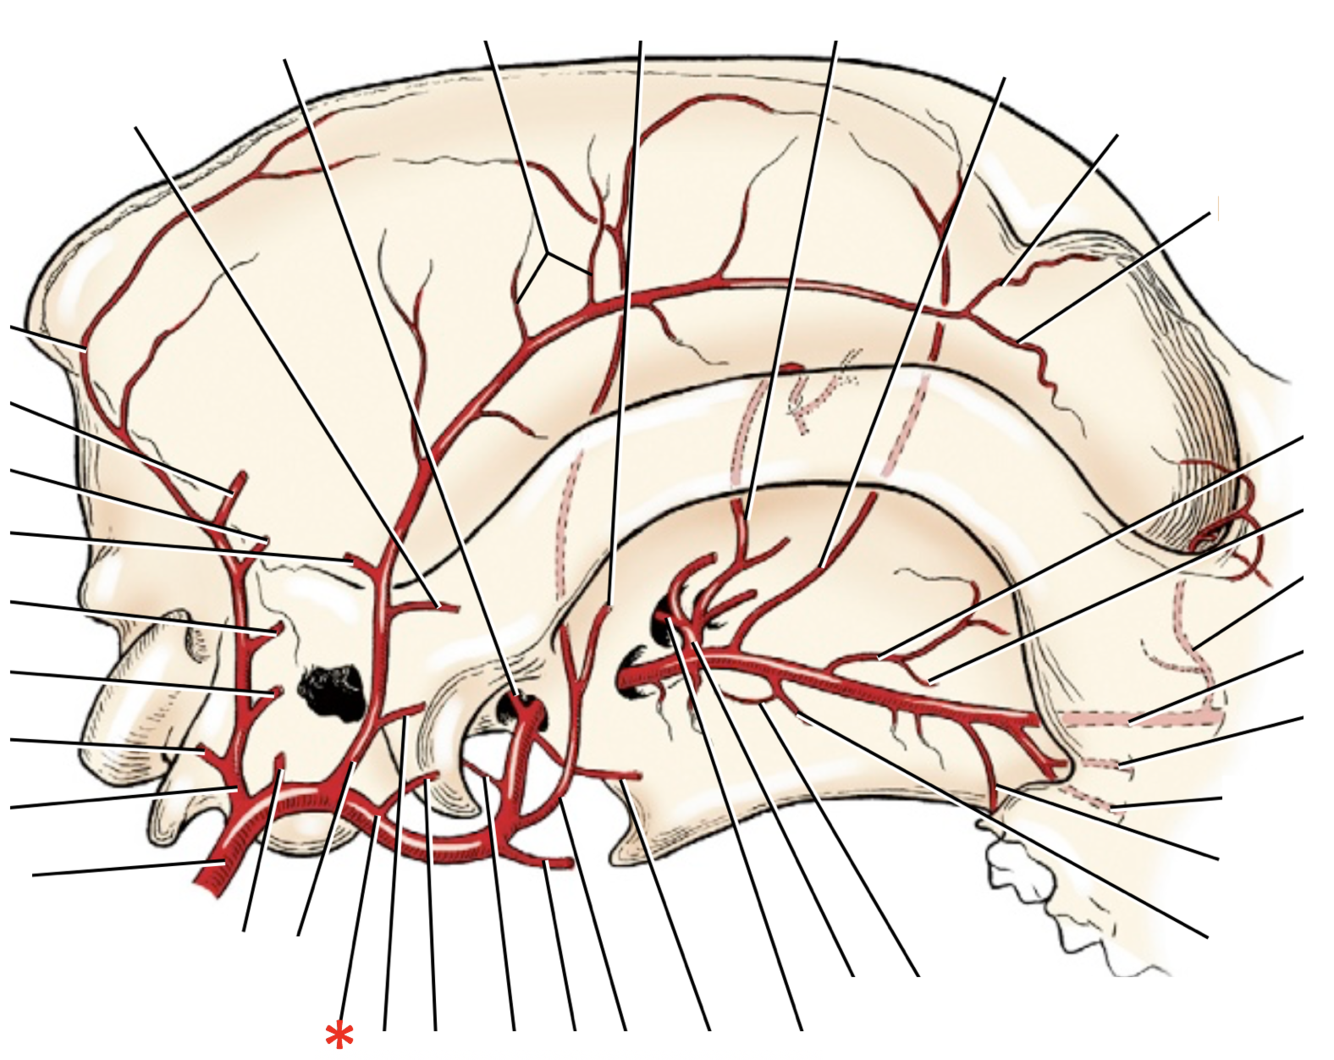

A. lingualis

A. facialis

A. maxillaris

A. auricularis caudalis

A. occipitalis

A. sublingualis

A. temporalis superficialis

A. facialis

A. cariotis externa

A. maxillaris

A. auricularis caudalis

A. lingualis

A. facialis

A. laryngea cranialis

A. maxillaris

A. occipitalis

A. carotis externa

A. laryngea cranialis

A. lingualis

A. facialis

A. sublingualis

A. auricularis caudalis

A. temporalis superficialis

A. maxillaris

**A.** **facialis**

**A.** **lingualis**

**A.** **carotis** **externa**

**A.** **carotis** **communis**

**A.** **carotis** **interna**

**A. lingualis**

**A.** **laryngea** **cranialis**

**A.** **auricularis** **caudalis**

**A.** **maxillaris**